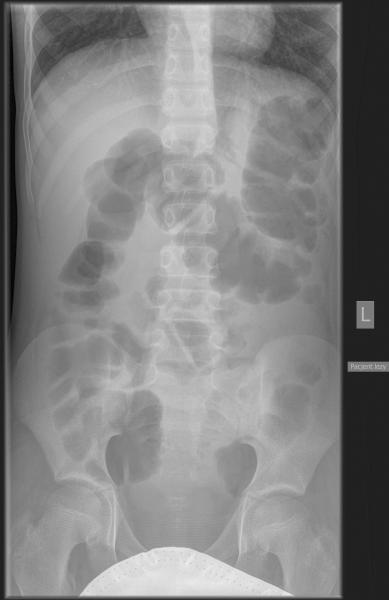

Przypadek 4: 11-letni chłopiec z napadowymi bólami brzucha od 3 tygodni, z wielokrotnymi wymiotami. Pacjent ani rodzice nie potrafili określić kiedy było ostatnie wypróżnienie. Podejrzenie niedrożności przewodu pokarmowego.

Rozpoznanie: Liczne poziomy płynu w dystalnych pętlach jelita cienkiego oraz w miernie rozdętym jelicie grubym do wysokości zstępnicy, brak powietrza w rzucie odbytnicy - cechy niedrożności. Bez cech perforacji.